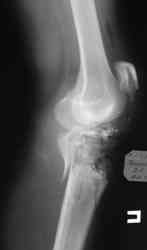

Уважаемые коллеги! На консультацию обратилась женщина, 23 года. В феврале огнестрельное ранение колена. Снимки первичные и майские в приложении. А также внешний вид раны. Укорочения конечности нет. Разгибание в коленном суставе отсутствует. Сгибание сохранено. Нестабильности нет.Дно раны - мертвая кость.

по снимкам у пациентки на данный момент сохраняется дефект наружного мыщелка б\б кости, который со временем приведет к вальгусной дефеормации голени и в настоящий момент практически отсутствует бугристость б\б кости, т.е. зона прикрепления собвственной связки, которую можно в принципе выкроить из средней порции сухожилия 4-хглавой со средней частью надколенника, но сначала необходимо запонить дефект костной ткани, либо путем свободной кости пластики, либо формированием отщепа б\б кости с микродистракцией в КДА Илизарова. т